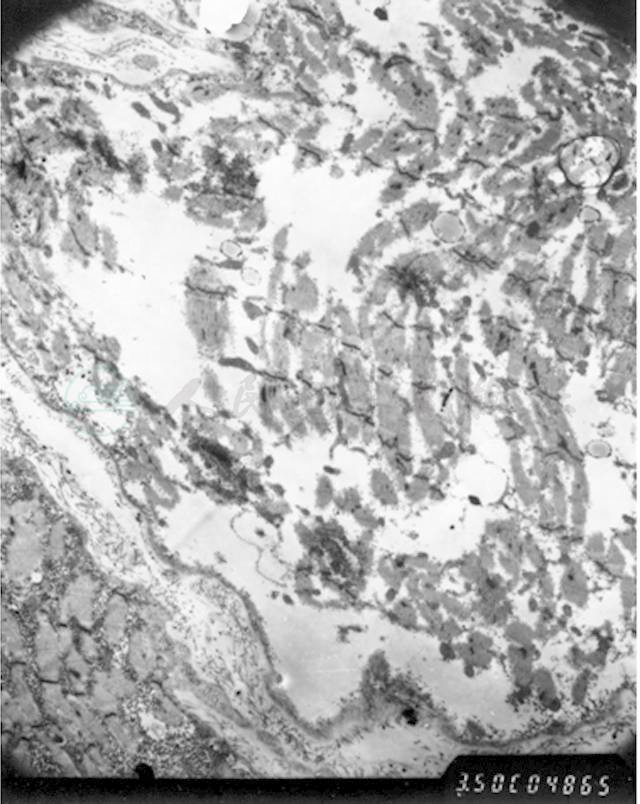

图5 肌活检(电镜)

肌纤维严重变性肿胀,肌丝结构模糊,部分肌纤维坏死,肌节结构消失,肌丝溶解,甚至整个肌纤维空泡化,仅存肌膜,呈空袋状。肌膜下、肌原纤维间可见大量糖原聚集(箭头所指)。细胞核多见固缩、变性